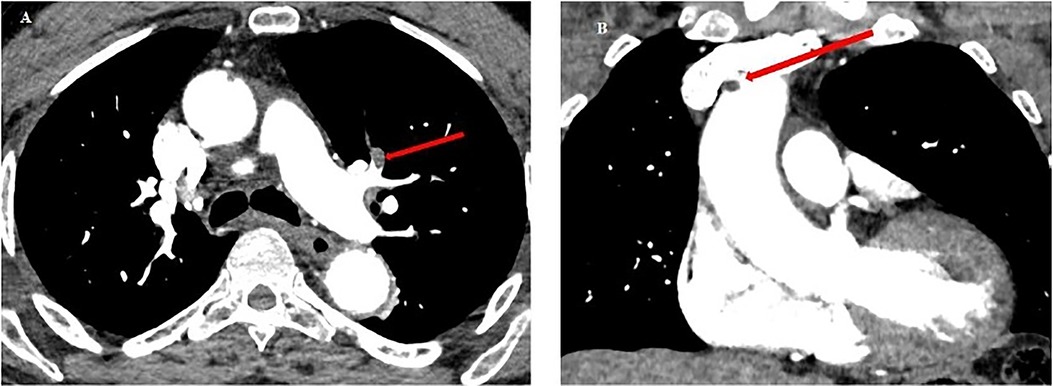

Figure 6

Figure 6. Chest CT scan from patient no.2. (A) Red arrow: pulmonary embolism of the upper lingular segment. (B) Red arrow: thrombus in the lumen of the ascending aorta (5 mm diameter), and of the aortic arch at the level of the birth of the brachiocephalic arterial trunk (6 mm).

In response to the imaging findings, the patient was given a second and third 10 ml dose of Bothrofav® at the 12-h and 15-h marks, respectively. After reporting a subjective sensation of a headache without any neurological deficit 22 h post-bite, a cerebral MRI was performed (Figure 7). The MRI detected multiple strokes, especially involving the PICA and junctional territories. Furthermore, due to the alarming rise in troponin to 18,451 pg/ml by the 19th hour, a cardiac MRI was carried out on Day 3. This MRI revealed a T2 hypersignal and late transmural lateral basal enhancement, indicative of a recent microvascular event. Multiple areas displayed late mediomyocardial or cocardial enhancement with fibrotic signs, suggesting cardiac amyloidosis (identified coincidentally) or myocarditis (Figure 8). However, unlike in the Patient No.1 case, the ECG did not exhibit any disruptions from the myocardial damage. After six days of hospitalization, the patient was discharged without any clinical aftereffects. He regained his physical activity level, matching his pre-envenomation state.